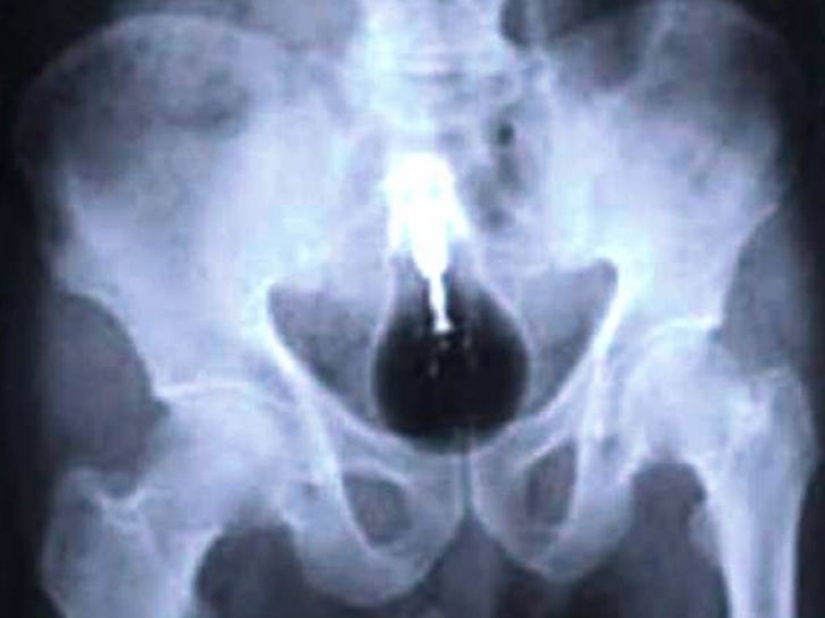

Y los presos de la ingestión de un teléfono celular.